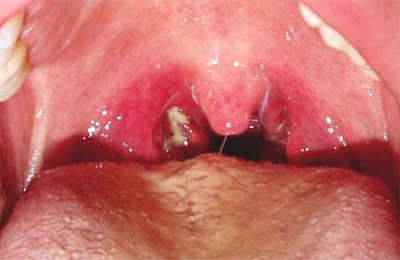

• налет, гной, сильное воспаление миндалин;

• горло болит только с одной стороны, в нем появляется набухание;